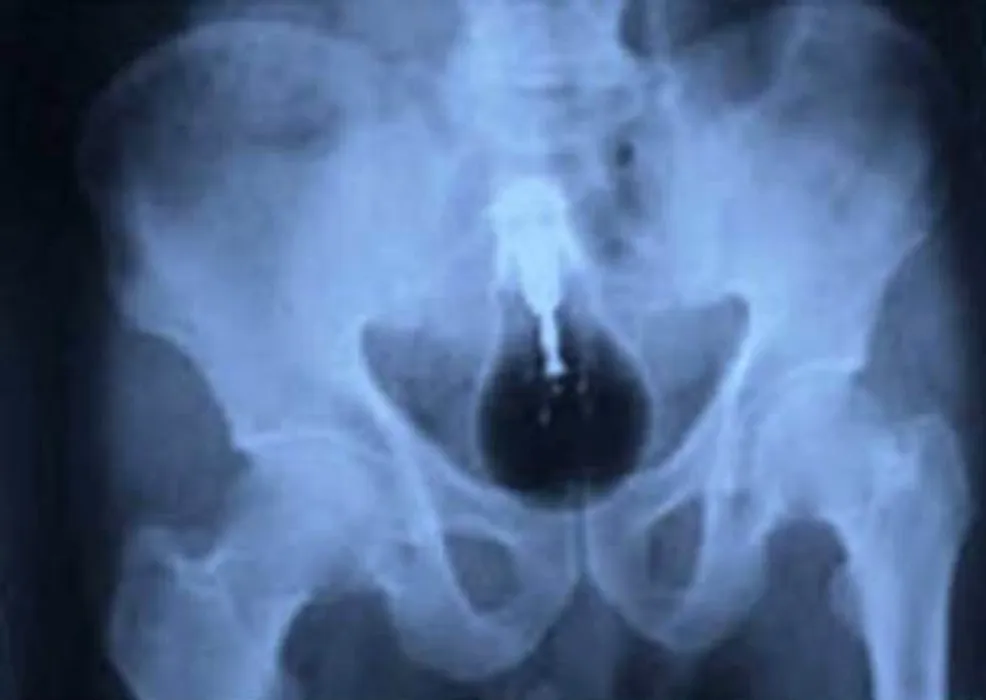

Cele mai ciudate lucruri pe care doctorii le-au găsit în stomacul pacienților. GALERIE FOTO